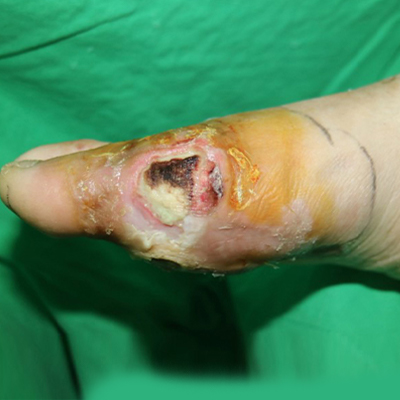

動脈性潰瘍(缺血性潰瘍)

發生在足部所有循環不良的部位 *照片版權為張舜程醫師所有,翻印必究。

糖尿病足 *照片版權為張舜程醫師所有,翻印必究。